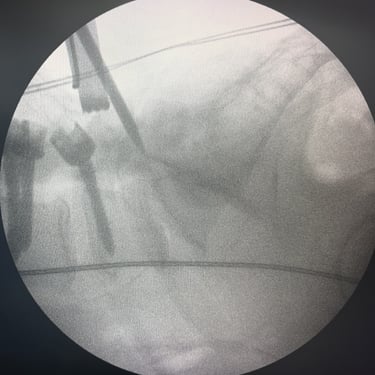

Columna lumbar inestable con listesis: tratamiento con artrodesis y tornillos transpediculares

La listesis lumbar ocurre cuando una vértebra se desplaza hacia adelante o hacia atrás respecto a la vértebra inferior, generando inestabilidad de la columna lumbar. Esta condición puede causar dolor lumbar crónico, compresión nerviosa, ciática, debilidad en las piernas o dificultad para caminar. Cuando el tratamiento conservador no es suficiente, la artrodesis lumbar con tornillos transpediculares es una alternativa quirúrgica eficaz. Este procedimiento permite fijar las vértebras afectadas mediante implantes que estabilizan la columna y favorecen la fusión ósea. Con técnicas modernas y abordajes mínimamente invasivos, se logra aliviar el dolor, mejorar la estabilidad vertebral y recuperar la función del paciente.